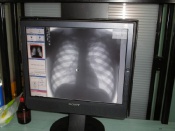

235 жителей Назарово прошли бесплатное флюорографическое обследование

235 жителей Назарово прошли бесплатное флюорографическое обследованиеВ Назарово подвели итоги Дня борьбы с туберкулезом. С 20 по 23 марта в разных районах города работала передвижная флюорографическая станция. Все желающие жители города могли пройти обследование бесплатно.

Медработниками было обследовано 235 человек, у 5 выявлены изменения различного характера: 1 человек выявлен с пневмонией, 2  с подозрением онкологического заболевания легких и 2 случая с подозрением на туберкулез.  Теперь этим пациентам необходимо обратиться к специалистам за назначениями курса лечения.